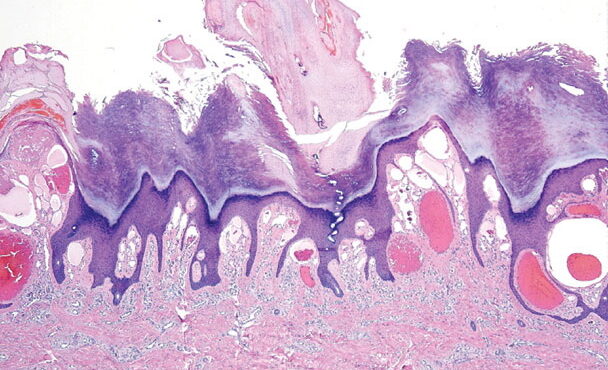

Read MoreVellus hair cysts = كيسات الشعر الزغبي OLYMPUS DIGITAL CAMERA